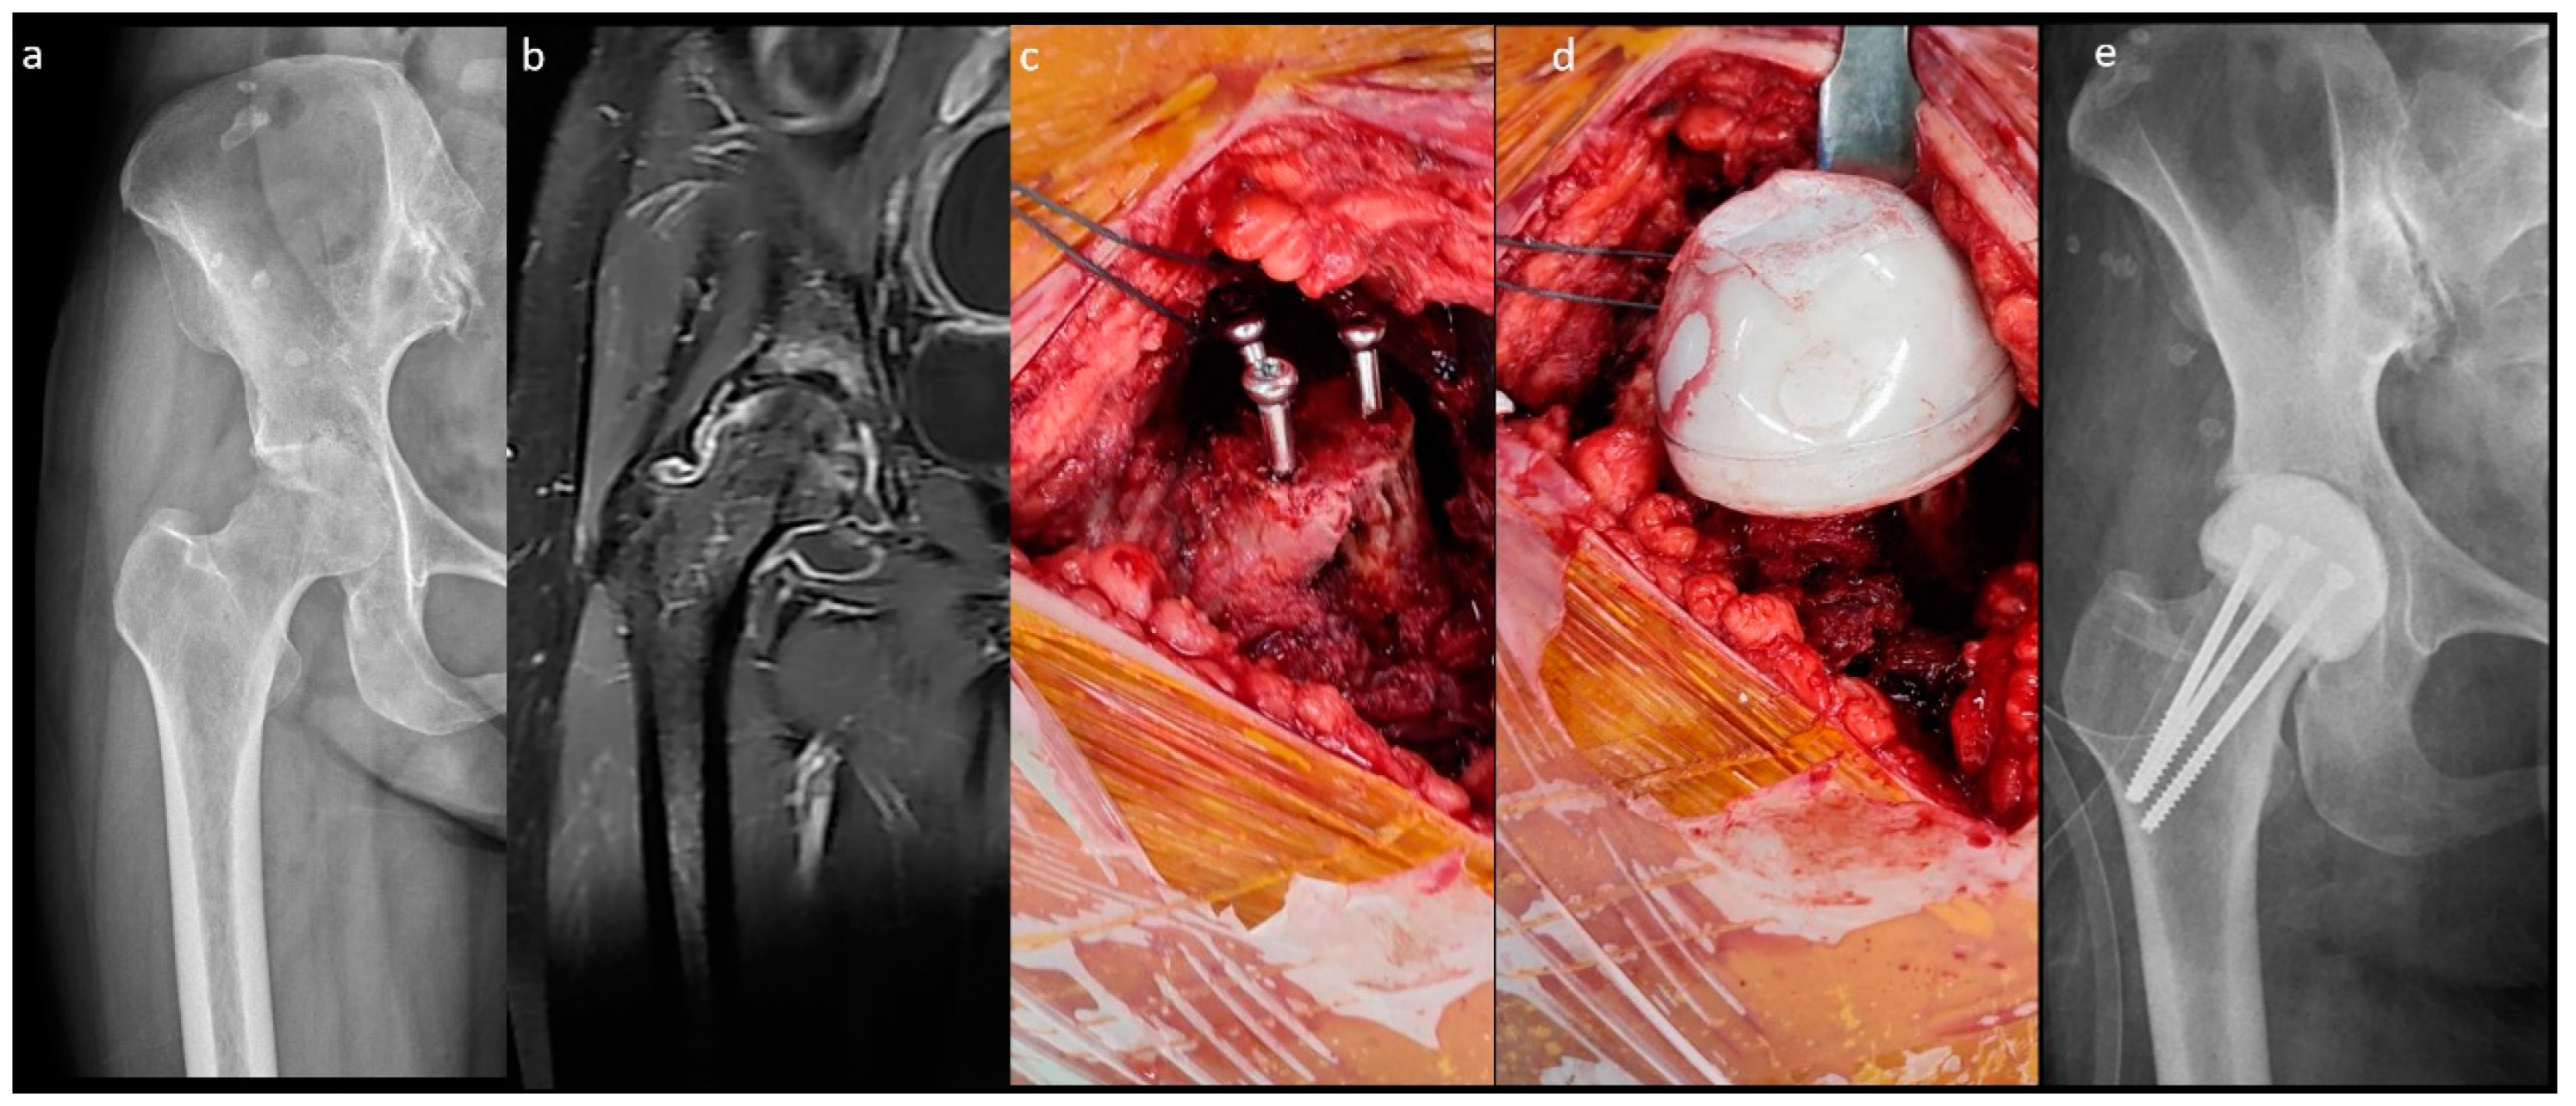

Figure 1.

Non-medullary-sparing (n-MS) spacers. (A) Pre-operative radiograph showing cartilage destruction with the subchondral collapse of the femoral head, (B) pre-operative MRI showing diffuse fluid accumulation within the joint, (C) fabrication of the n-MS spacer using a silicone mold, (D) the hip joint with the n-MS spacer implanted, and (E) post-operative radiograph with the n-MS spacer in situ.